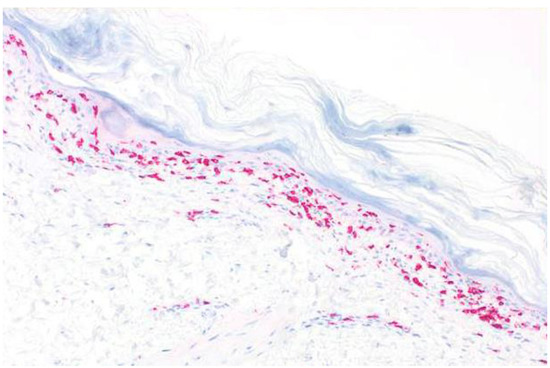

2. Case Report